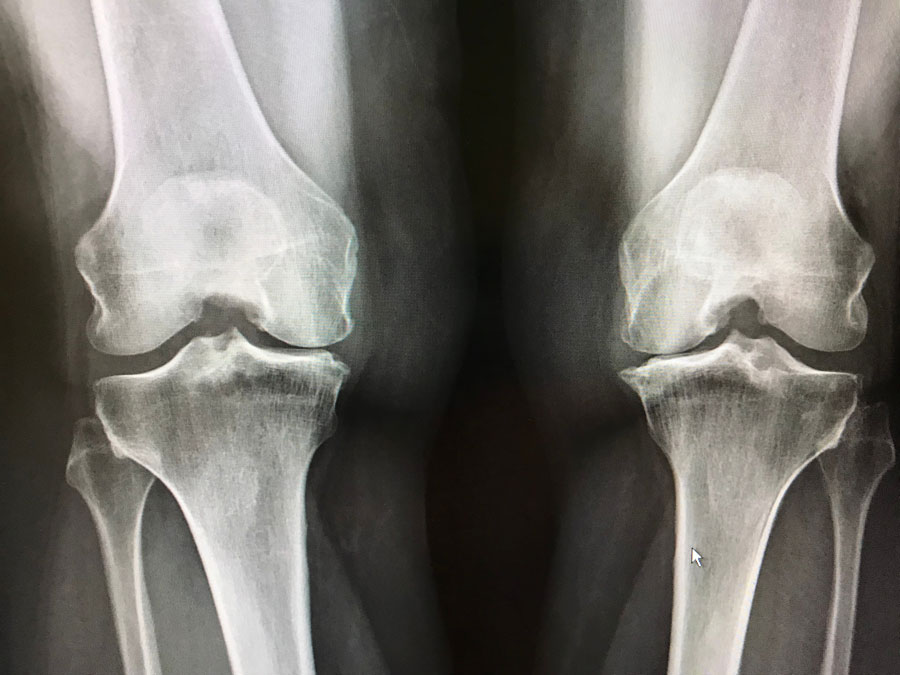

Utilización de la atención médica y mortalidad en personas con artrosis en el Reino Unido

17 julio 2023

Las personas con osteoartrosis tuvieron mayores tasas de consultas de médicos de cabecera, ingresos hospitalarios y mortalidad por todas las causas que variaron entre los sitios conjuntos. Br J Gen Pract,, 10 de julio de 2023